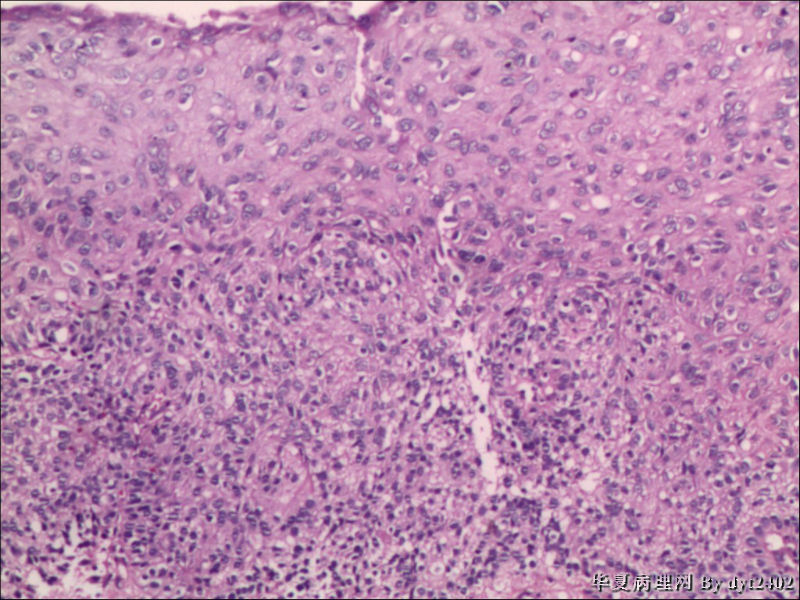

• 宫颈活检 其中一点较迷糊图2

图2

四点中三点是CIN iii,另一点怀疑有更重病变

这个病人是44岁,去年11月底阴道脱落细胞、TCT均见细胞异常,建议活检,病人犹豫,接着单位组织到外院体检时做阴道镜正常,后霉菌感染,此时宫颈未涂醋肉眼看还光滑,直至今年3月来做活检,事前做白带检查又见异常细胞,宫颈未涂醋见后上唇白上皮,涂醋酸后上下唇都有厚白上皮,镶嵌,夹活时上皮剥脱,未能夹到间质,阴道镜医生说至少有CIN III 到原位癌了。。镜下其中3点CIN III无疑,唯有9点处如6、7、11、14等所示结构,但我未见间质浸润,不能说是浸润癌,不知道有没基底细胞样鳞癌的可能,我发了个原位癌不除外深部有更重病变,。